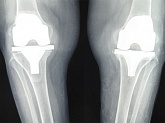

Endoprothetik des Kniegelenks

In den späten Stadien der Arthrose des Knies durch eine ausgeprägte Begrenzung der Bewegung begleitet, konstant starke Schmerzen, körperliche Unversehrtheit Verformung bis zur Genesung der einzige Weg ist der Ersatz des betroffenen Gelenks für eine künstliche - Endoprothetik.

Diese Methode ermöglicht es Ihnen, die richtige Form des Gliedes, eine vollständige Palette von Bewegung im Gelenke, zu entlasten ständige Schmerzen und Knirschen bei Bewegung und als Ergebnis wieder herzustellen, signifikant dem Patienten Lebensqualität zu verbessern.

Im Folgenden sind Röntgenaufnahmen und Fotografien, die die Strecke der Bewegung in der betroffenen Gelenke vor und nach der Operation veranschaulichen.